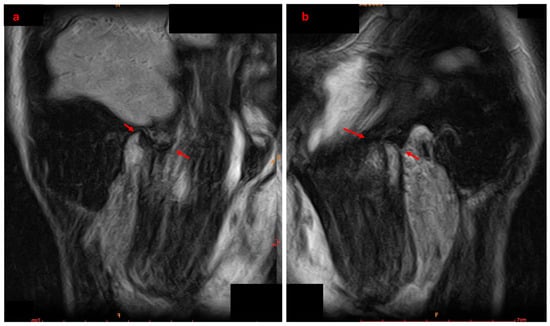

An Innovative Approach to Managing Temporomandibular Disorders Through the Combined Use of Two Oral Devices: A Case Report

by Antonio Spagnuolo, Roberta Iacono, Gian Mauro Liberatore and Carlo Di Paolo

Appl. Sci. 2026, 16(1), 273; https://doi.org/10.3390/app16010273 - 26 Dec 2025

Temporomandibular disorders (TMD) are increasingly prevalent in the adult population. Given the multifactorial and often chronic nature of TMD, the ideal therapeutic approach must be multimodal and personalized, with a preference for conservative treatments. However, standardized protocols combining occlusal devices and biobehavioral therapy for internal derangement (ID) are still lacking. Case Presentation: A 20-year-old male patient presented with bilateral anteromedial reducible disc displacement, with intermittent locking on the right. He reported joint noises, difficulty chewing, and occasional painful mouth opening. A comprehensive diagnostic workup, including clinical, functional, and radiographic evaluations, was performed. The patient underwent a biobehavioral gnathological therapy involving two oral devices: RA.DI.CA. and By-Te ® Reali. The protocol included personalized exercises, patient education, and behavioural counselling. Results. The patient achieved full remission of pain, disappearance of joint noises, and restoration of mandibular function, without dental movement. Pre- and post-treatment MRI and condylography confirmed improved condyle-disc relationships, increased intra-articular space, and better symmetry of movements, particularly on the right. Conclusion. The combined use of RA.DI.CA. and by-Te ® Reali devices, supported by a personalized functional programme, appears effective in managing TMD with ID. Further studies on larger populations are needed to confirm the efficacy and safety of this protocol. Full article